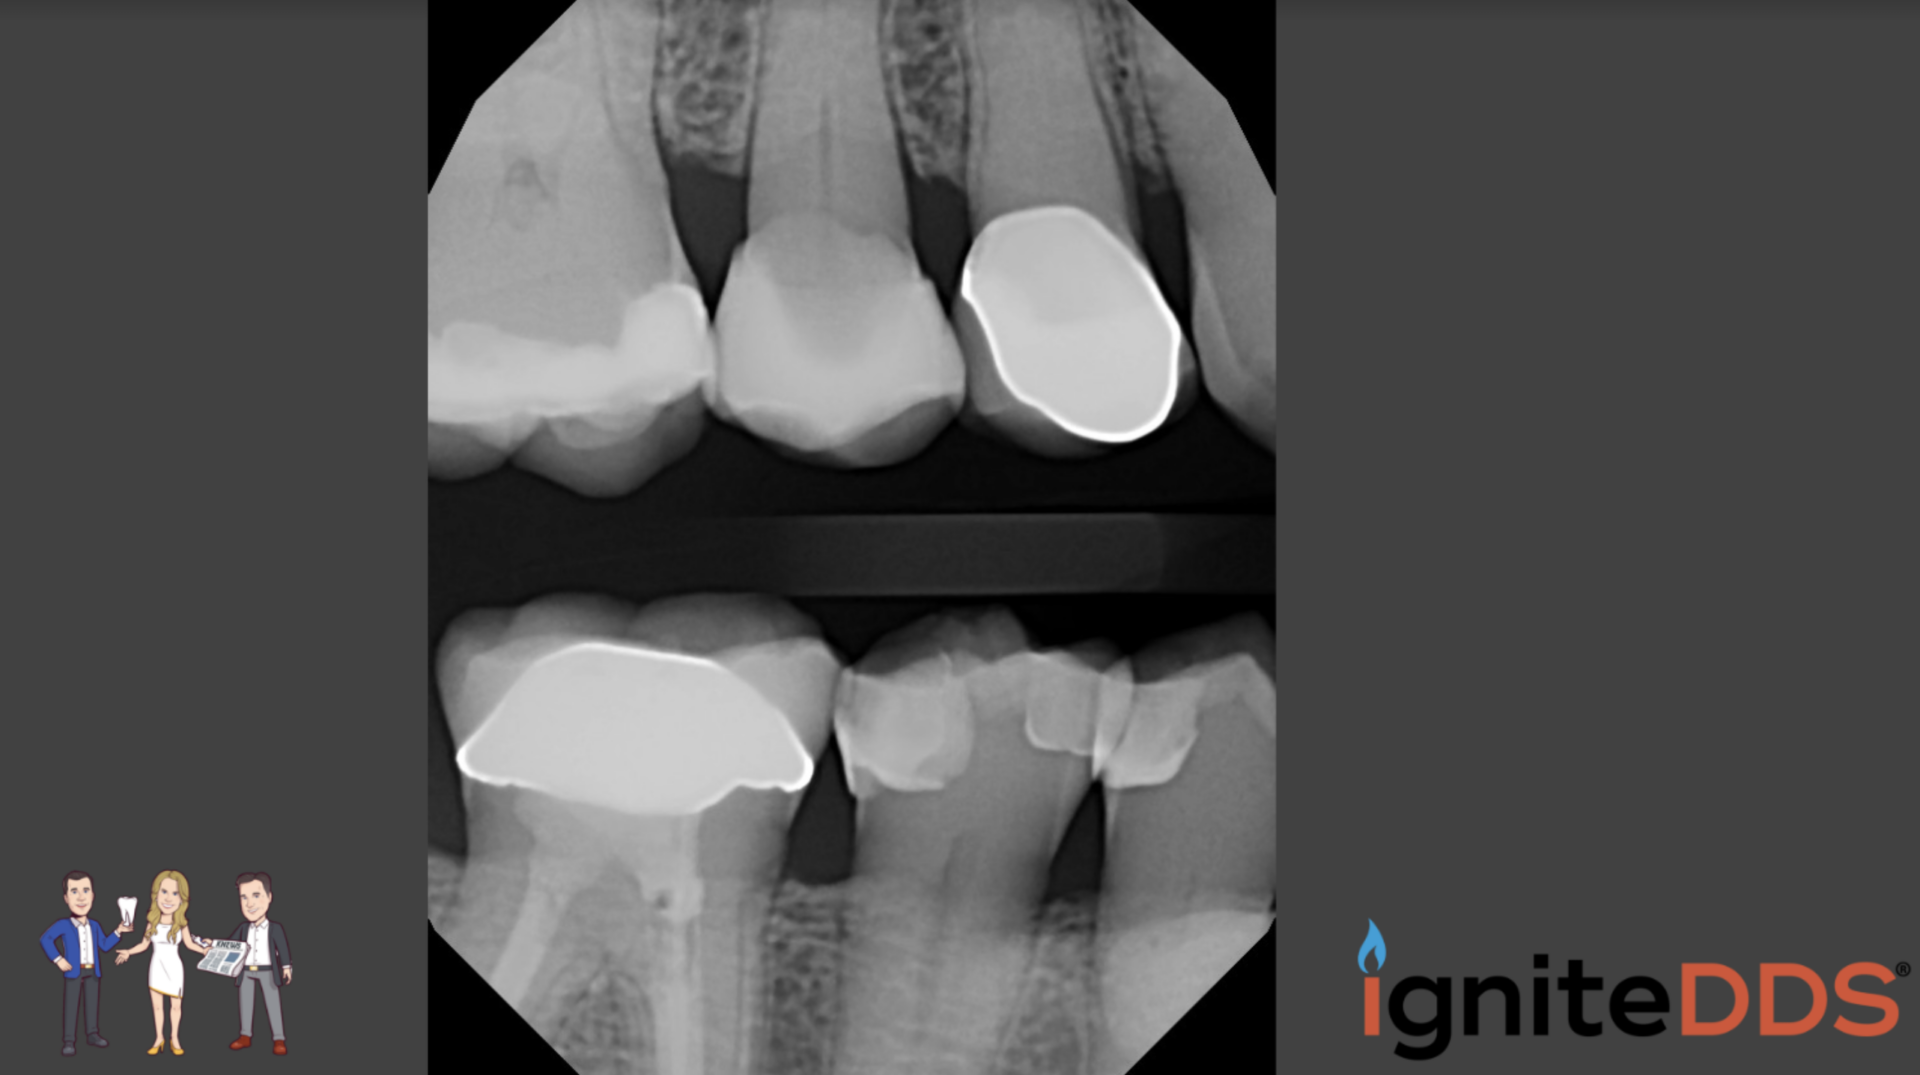

From ignitedds.com

Fractured Tooth Case Study igniteDDS Tooth Fracture X Ray Odontoid process fracture, also known as a peg or dens fracture, occurs where there is a fracture through the odontoid process. Mandibular fractures represent two thirds of all maxillofacial fractures. Radiographic examination is essential to identify the location and extension of the fracture. The maxillary incisors are the most commonly injured tooth. Dental trauma is commonly classified as 1,2: Dental. Tooth Fracture X Ray.